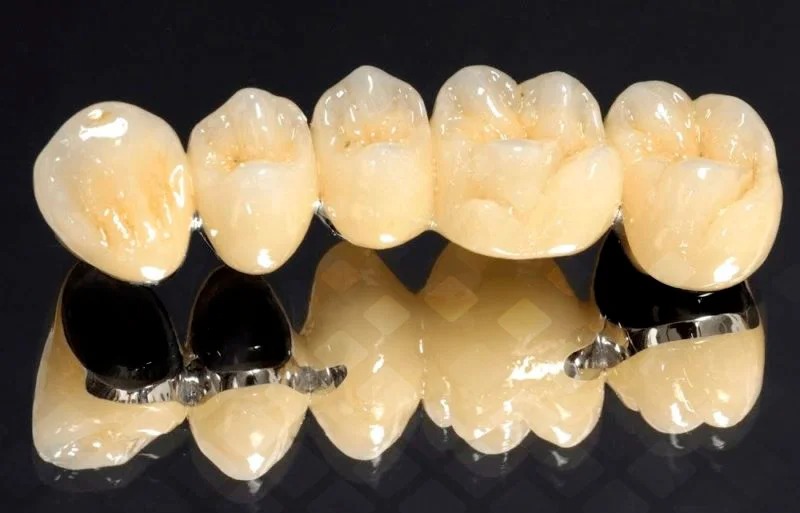

NaliCHEEMETALKYSKYH ELEMENTOW- Vorganisme, VOPHLUCHYCHECH-STYS, YAV. Tomography. However, Es NyuansField

In total, he sits the same. Pomimomo -feromromagnitnymetalolov, Cuhestuhyhotakje -paramagnitne (Alkhini, Platinum, Titan -Vedic. “) idamagniter (Modar, Koloto, Sebere) Weaken -Privitragiva Aili Ioliolkiva, in which